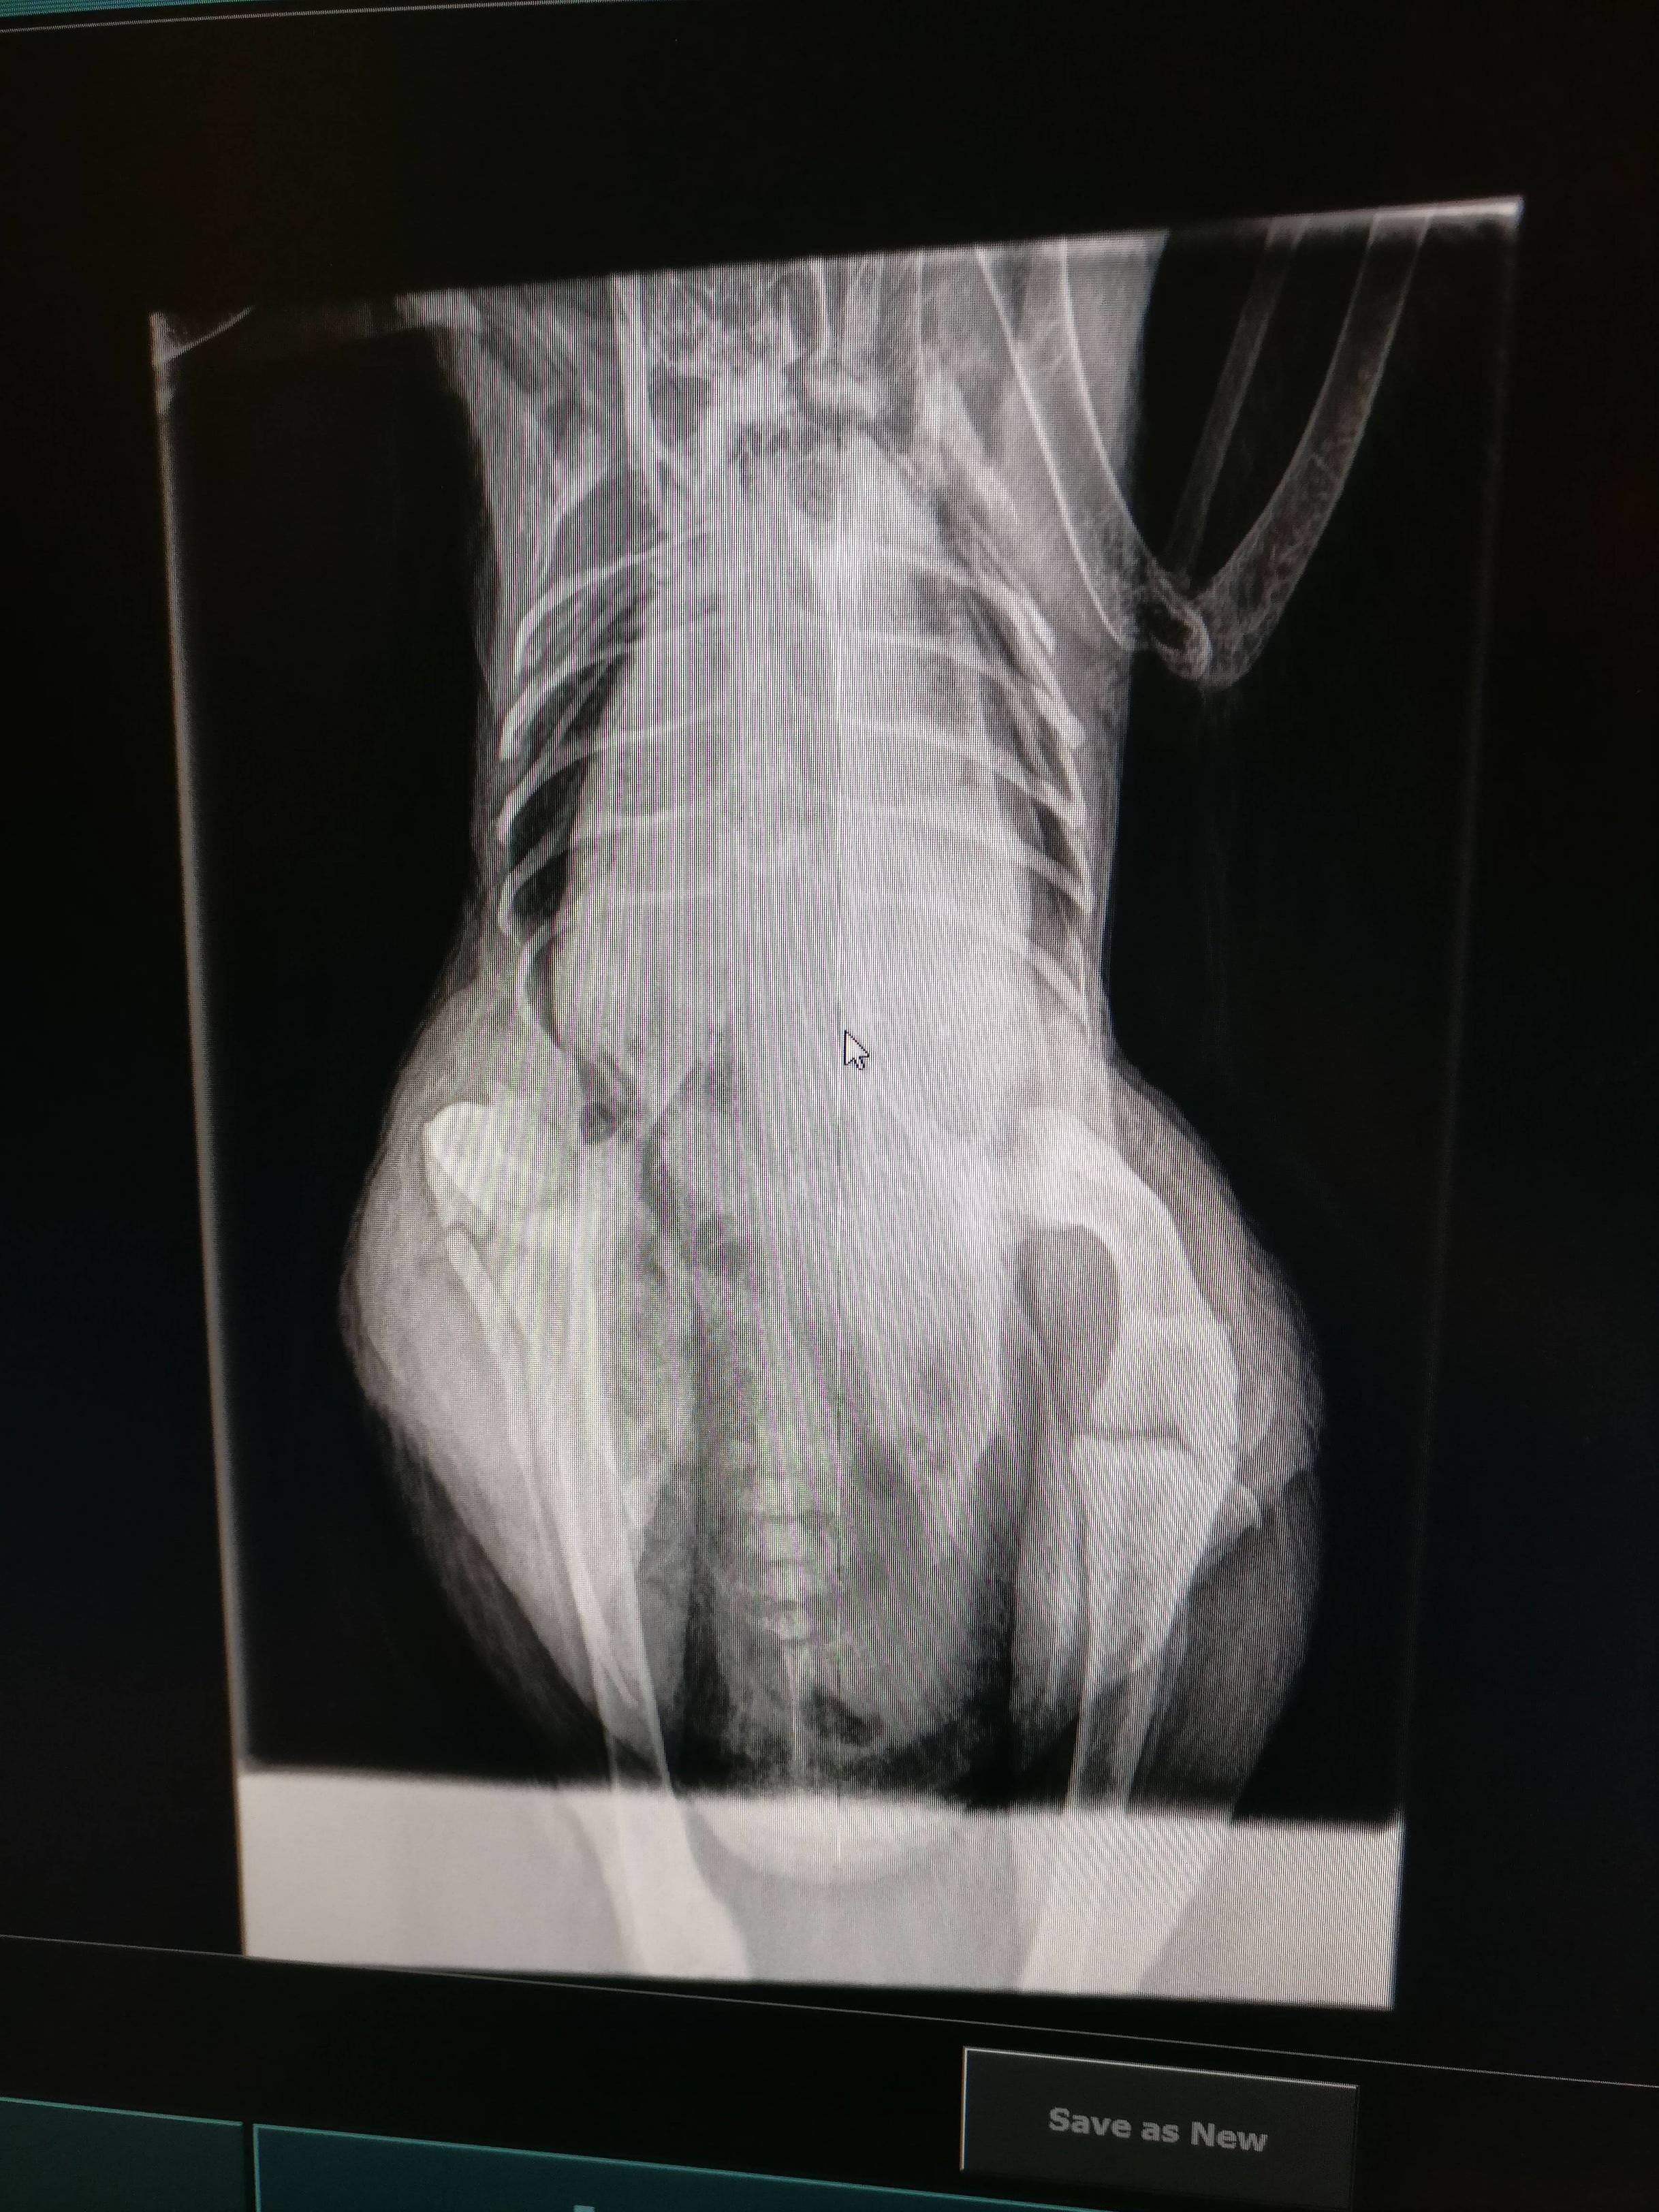

- Gloved finger insertion into vent to feel for egg, feeling towards the uterus as per images in post #12. Identification of bound egg.